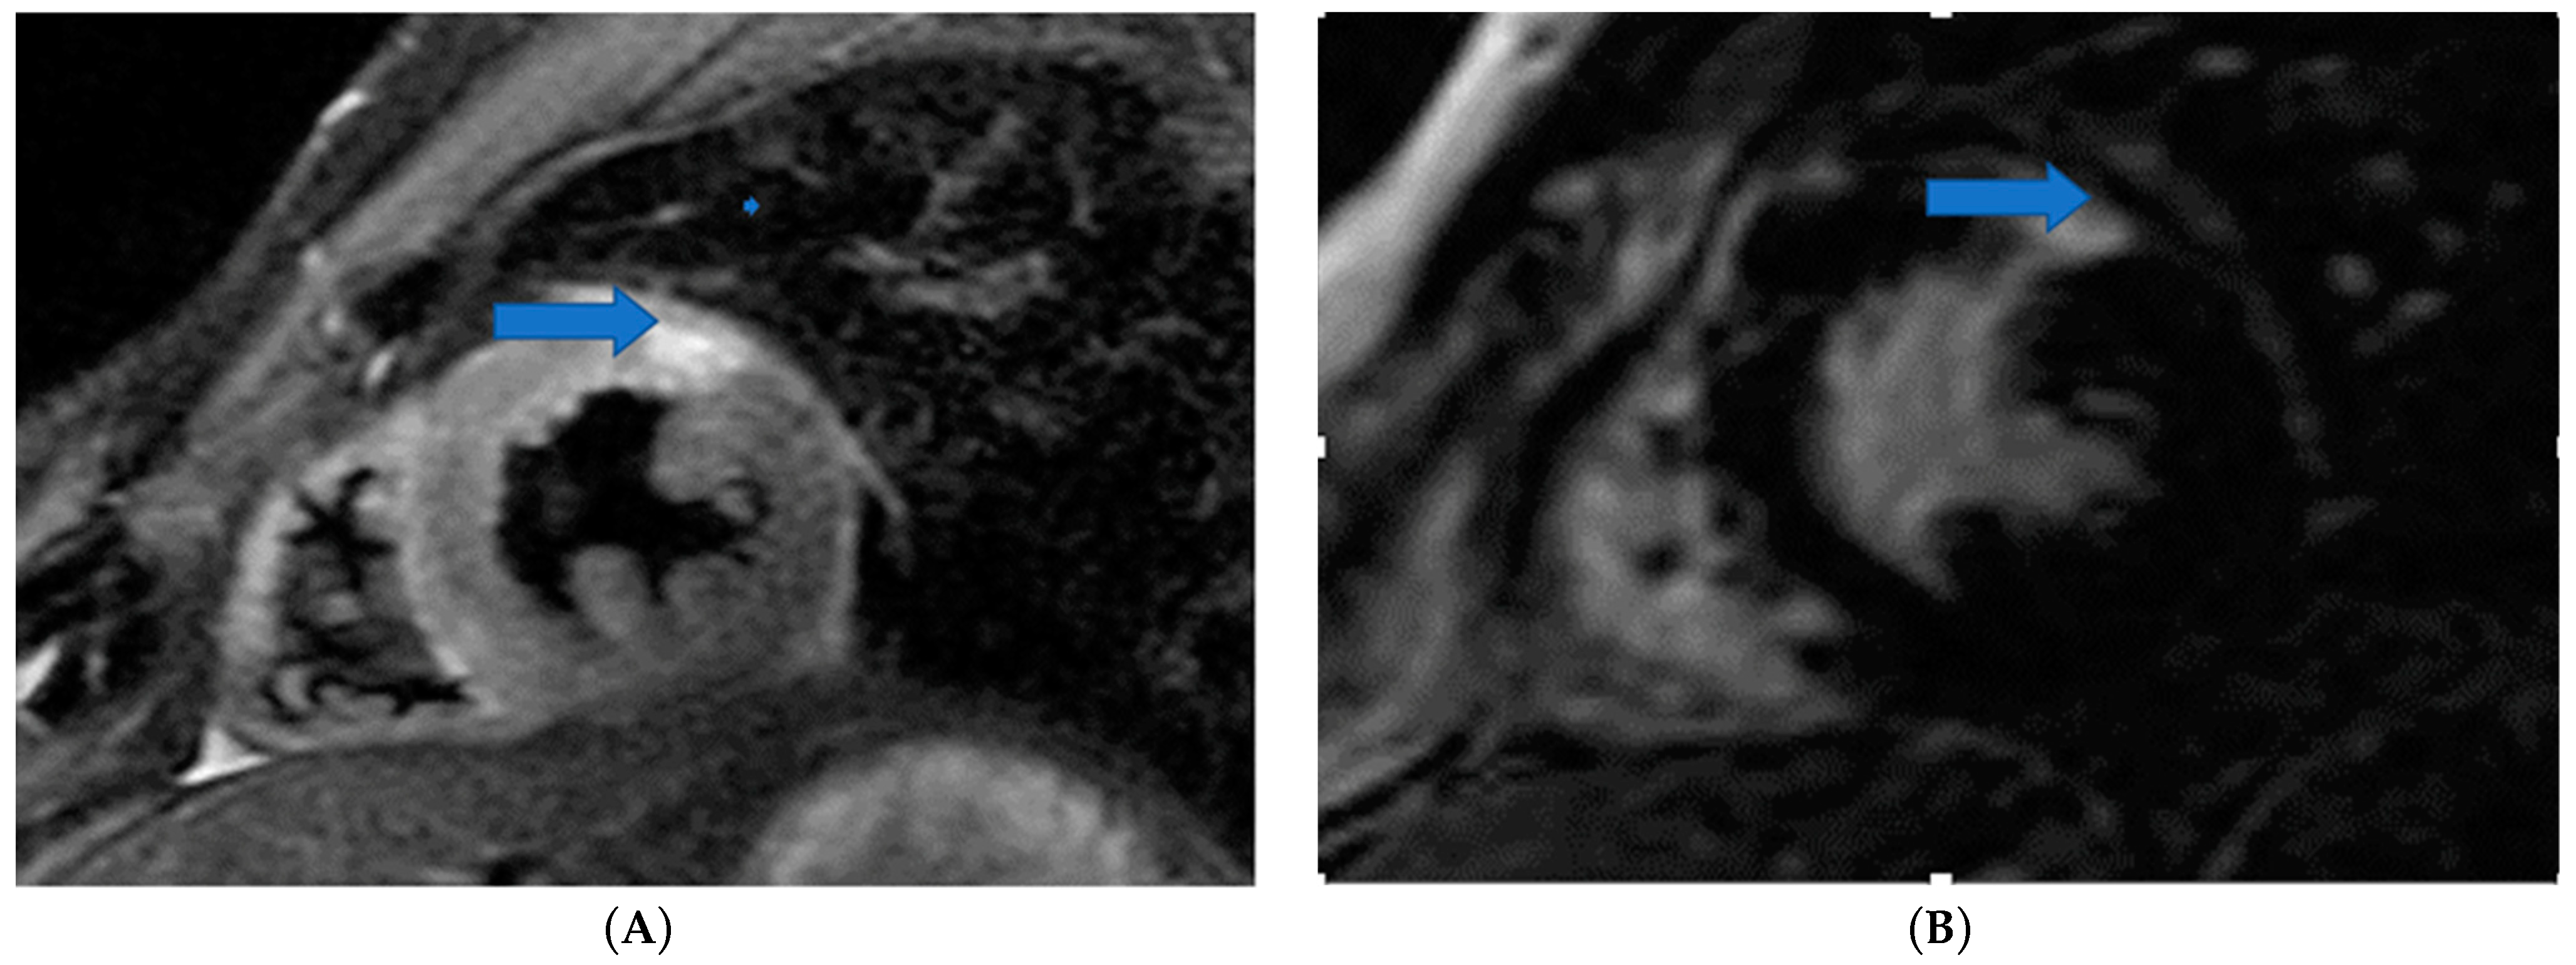

4.5. Myocardial Edema-Fibrosis Assessment